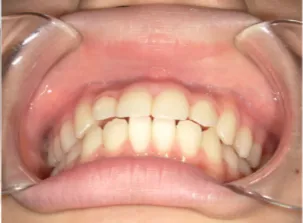

治療前①小2:8y1m 初診

| カウンセリング・診断結果 | 前歯が受け口になっていているため、適正な成長へ誘導するために前歯の咬み合わせの改善が必要なことを説明し、診断を希望されたので精密検査へ進みました。 精密検査の結果、骨格的には受け口傾向、下顎前歯の突出、上下ともアーチが小さく凸凹(叢生)が認められ、機能的には低位舌と口唇閉鎖不全があり、口元は上下唇とも突出していますがコンケーブになってないことがわかりました。 |

| 行ったご提案・診断内容 | 成長期に行う治療と咬合治療をご提案 咬合治療でOPEにならないように、成長期に受け口の悪化予防を行い、咬合治療で歯並びと口元の改善を行うことを提案しました。 《成長期治療:成長時期にお口の環境を整え、適正な成長を誘導する治療》 使用装置 《咬合治療:成長期治療後に大人の歯を咬ませる治療》 *治療は上記ステップで行いました。 《治療後の経過観察》 |